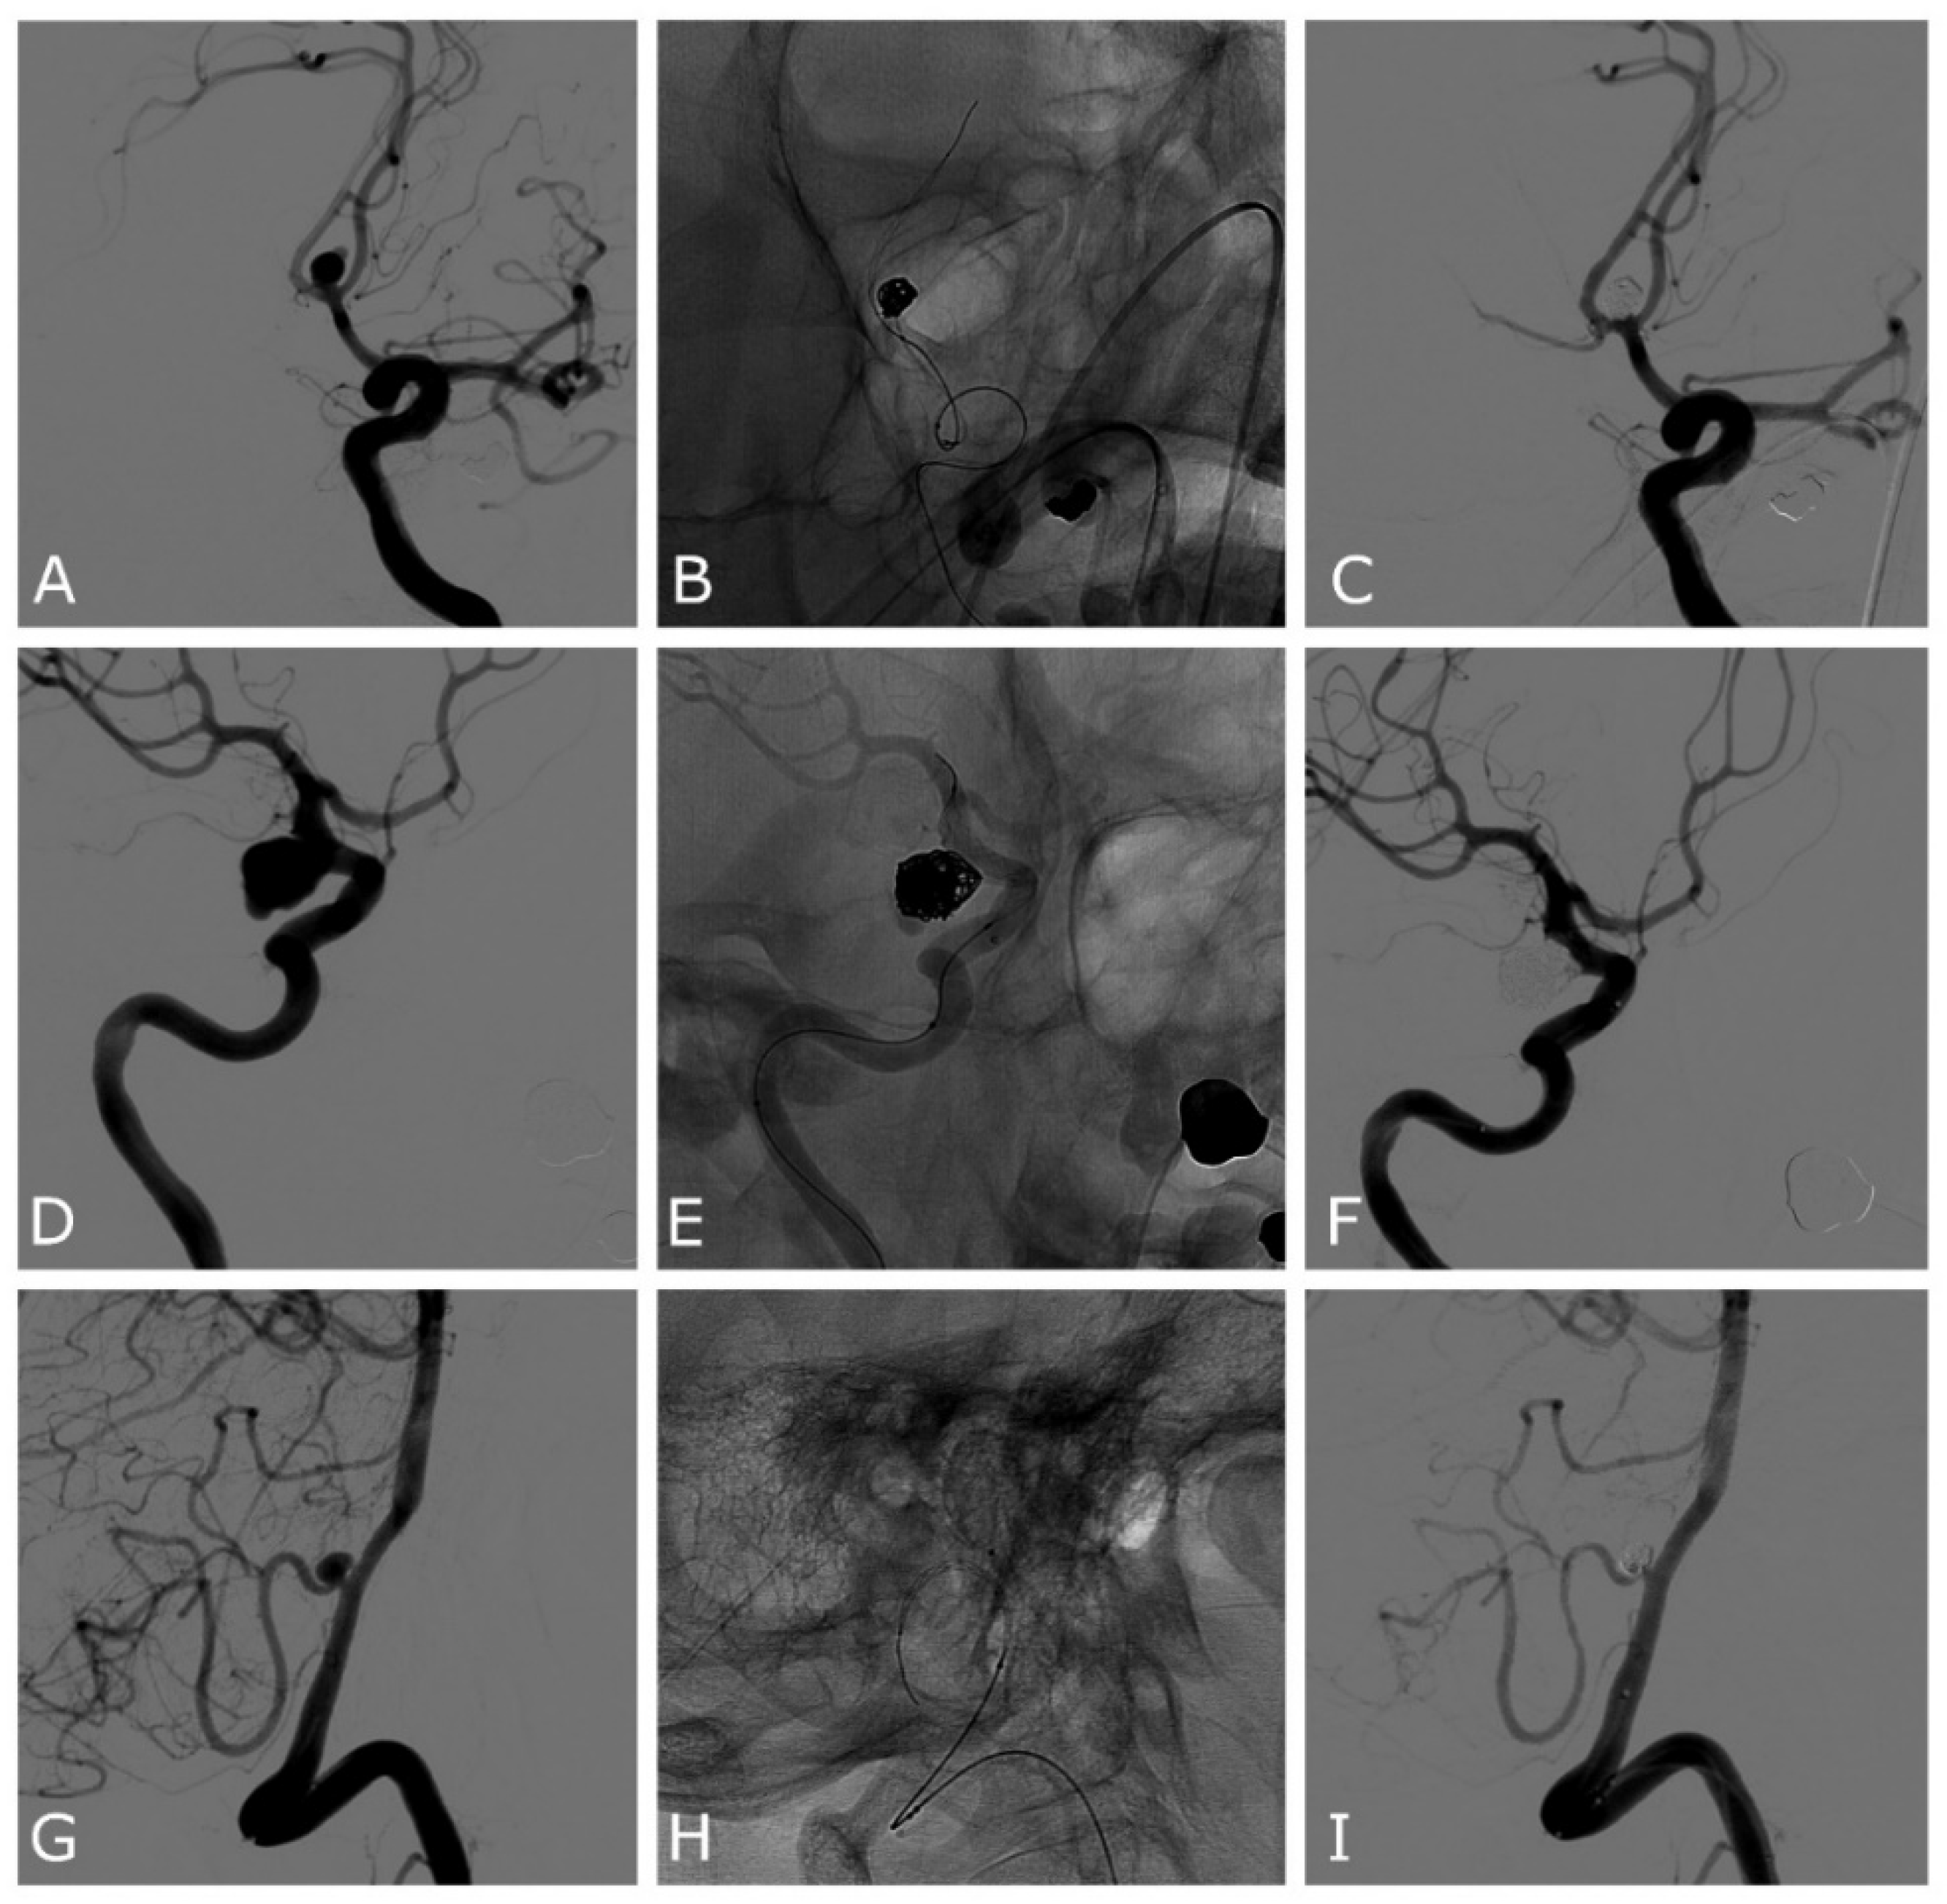

| Case | Age | Sex | Location | SAH | Max Size (Height, Width, Neck) mm | Device | Complications | Rescue Treatment | mRR | mRs at 3 Months |

|---|---|---|---|---|---|---|---|---|---|---|

| 1 | 74 | F | PCOM | No | 4.2, 7, 4 | Comaneci | - | I | 0 | |

| 2 | 65 | M | PCOM | Yes | 3.1, 4, 3 | 17 | - | I | 0 | |

| 3 | 70 | F | PICA | Yes | 3.5, 2, 1.5 | Comaneci | - | I | 0 | |

| 4 | 86 | F | PCOM | Yes | 6.4, 4.3, 5.5 | Comaneci | Intra-Comaneci and parent artery clot formation | Stent | II | 6 |

| 5 | 59 | F | ACOM | Yes | 10, 6.2, 5.5 | 17 | - | II | 0 | |

| 6 | 65 | F | PCOM | No | 6.7, 3.9, 3 | Petit | - | II | 0 | |

| 7 | 51 | F | MCA | No | 2, 2.2, 2 | Petit | - | II | 5 | |

| 8 | 65 | M | ACOM | Yes | 5.7, 3.7, 3.5 | 17 | - | 0 | ||

| 9 | 77 | F | PCOM | Yes | 8, 10.3, 5.9 | Comaneci | Intra-Comaneci clot formation | I | 0 | |

| 10 | 65 | F | ACOM | Yes | 3, 2.4, 2 | 17 | - | I | 5 | |

| 11 | 45 | M | ACOM | Yes | 5.5, 3.6, 2.8 | 17 | Intra-Comaneci clot formation | IIIb | 1 | |

| 12 | 62 | F | ACOM | Yes | 9, 4.5, 3 | 17 | Intra-Comaneci clot formation | Stent | IIIb | 0 |

| 13 | 55 | M | ACOM | Yes | 14.5, 15.6, 8.2 | 17 | - | I | 0 | |

| 14 | 61 | M | ACOM | Yes | 3, 5.9, 5 | 17 | Intra-Comaneci clot formation | II | 0 |